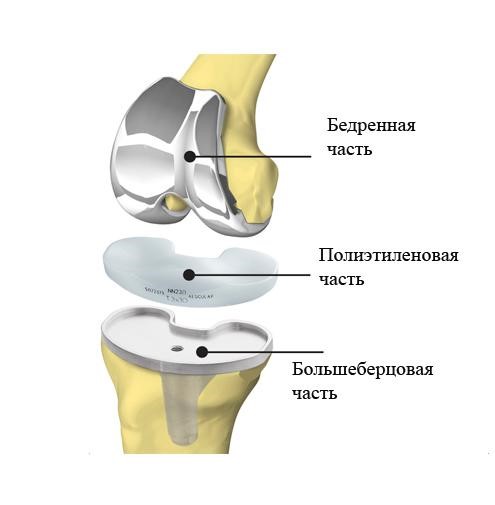

Фотографии и примеры протезирования коленного сустава